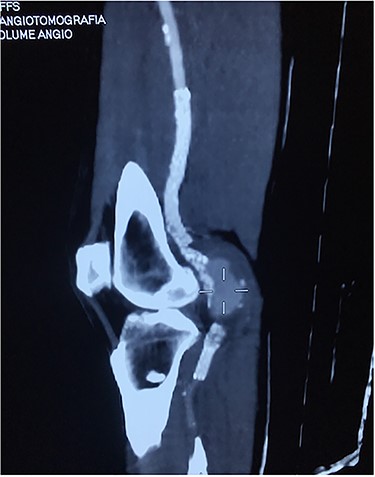

Based on the characteristics of the pseudoaneurysm, we decided on a minimally invasive interventional approach. This was in agreement with other vascular surgeons and the family. Under local anesthesia, the left common femoral artery was punctured in antegrade fashion, and an 8-F sheath was deployed. An X-ray of the popliteal region highlighted the stent fracture, and digital arteriography showed the large pseudoaneurysm. After administration of 5000 IU of heparin, a 0.035 guidewire was passed across the fractured stent and was placed distally in the posterior tibial artery. At the end of the procedure, a 7.0 × 150-mm self-expandable Viabahn endoprosthesis (W. L. Gore & Associates, Flagstaff, AZ, USA) was delivered into the stent, and adjuvant balloon inflation was performed with a 6.0 × 80-mm balloon leading to a complete exclusion of the pseudoaneurysm (Fig. 4). The final angiogram showed no residual stenosis, complete exclusion of the pseudoaneurysm, and no compromise of distal runoff. There were no complications associated with the procedure.

Viabahn endoprosthesis delivered after percutaneous intervention and immediately intraoperative angiogram.